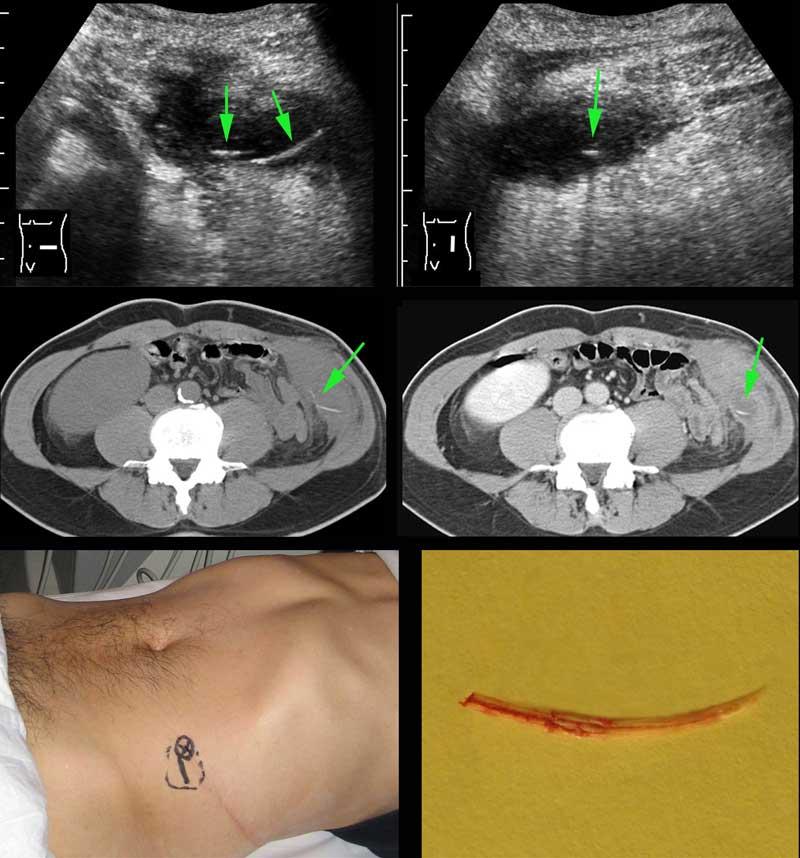

Bệnh nhân nam 53 tuổi nhập viện với khối đau hố chậu trái và CRP 173, nghi ngờ viêm túi thừa.

Bệnh nhân có tiền sử cắt thận trái 20 năm trước.

Siêu âm phát hiện áp xe thành bụng chứa một cấu trúc mỏng, đường cong (mũi tên).

CT không và có tiêm thuốc cản quang tĩnh mạch xác nhận xương cá (mũi tên) trong áp xe thành bụng có ranh giới không rõ ràng.

Lưu ý rằng xương cá có thể dễ dàng bị bỏ sót nếu chỉ chụp CT có tiêm thuốc cản quang tĩnh mạch.

Vị trí áp xe và xương cá được đánh dấu trên da.

Chỉ với một đường rạch rất nhỏ, mủ và xương cá đã được lấy ra. Hồi phục không biến chứng.